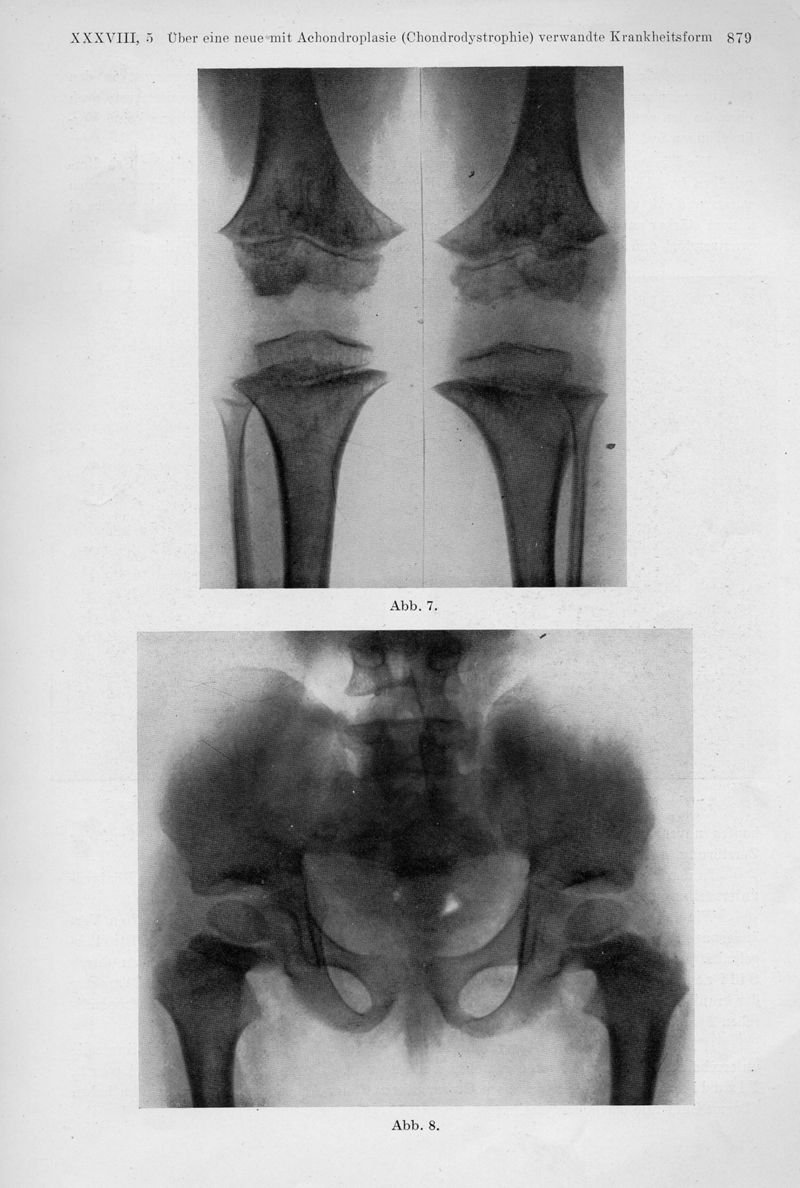

Über eine neue mit Achondroplasie (Chondrodystrophie) verwandte Krankheitsform. (Osteochondropathia multiplex Grudzinski, Achondroplasia atypica Silfverskiöld, Dystrophie spongieuse epiphysaire systematisée Ghimus)

In : Fortschritte auf dem Gebiete der Rontgenstrahlen, 1928, Vol. 38, pp. 873-82